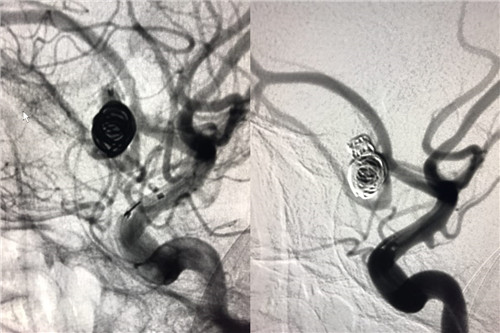

患者赵某,8月28日因“蛛网膜下腔出血”入住我院神经外科。入院时意识呈浅昏迷,且意识障碍进行性加重伴随右侧瞳孔散大,曲友直教授团队根据颅脑CT判定患者为动脉瘤引起的蛛网膜下腔出血。由于动脉瘤在人体内像个定时炸弹,随时会再次破裂,危险性非常大。能否及时为患者实施动脉瘤手术,避免动脉瘤继续破裂,从源头遏制患者病情继续恶化的可能性,直接关系到患者的预后。曲教授团队制定了详细的诊疗计划,在最短时间内为患者行侧脑室外引流术,并及时为患者实施了全脑血管造影,结果证实了术前判断,是大脑前交通动脉瘤,分上下两叶、宽颈。考虑到患者脑肿胀明显,基础状态差,急诊行开颅夹闭手术风险极高,曲友直教授团队反复评估、综合考虑后为患者实施了双导管技术宽颈动脉栓塞术。实施双导管技术避免支架辅助对前交通宽颈动脉瘤进行栓塞,术后患者无须长期口服抗血小板及抗凝药物、为患者术后赢得了进一步康复的机会、减少了长期服药的经济负担。手术过程十分顺利,术后患者病情稳定,正在进一步恢复治疗中。

术中造影

术后造影